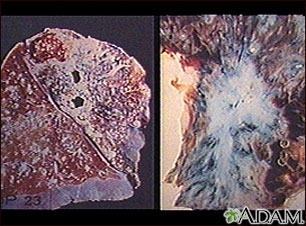

People with AIDS are also at higher risk for certain cancers, especially lymphomas and a skin cancer called Kaposi sarcoma.